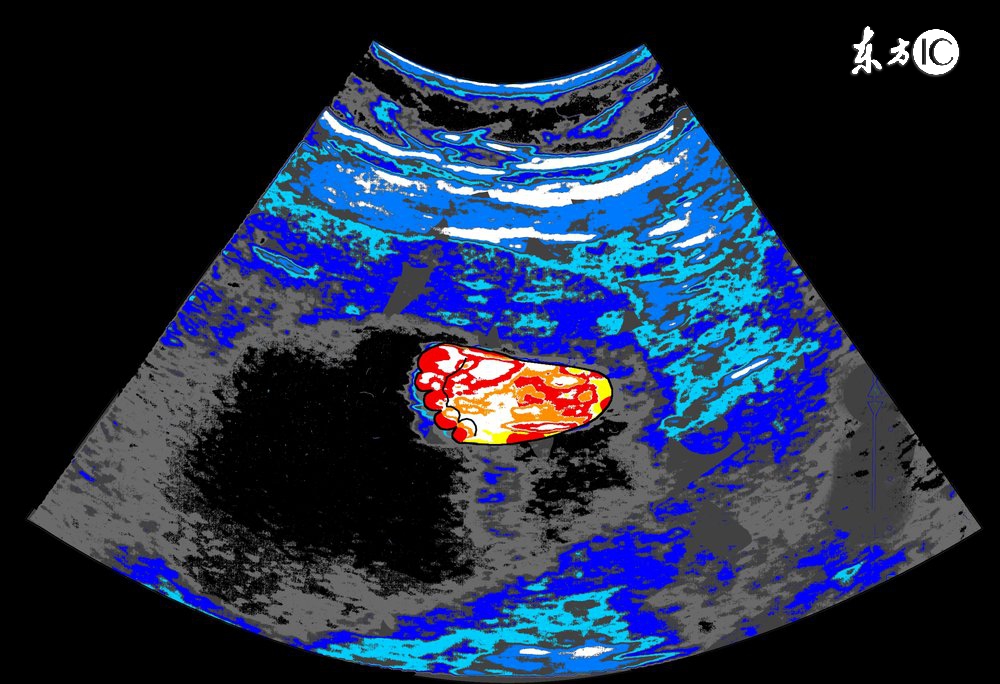

3、胎盘位置:

正常胎盘附着于子宫的前壁、后壁、宫底或侧壁,如果B超显示胎盘在子宫下段,甚至胎盘下缘达到或覆盖宫颈内口处,即为前置胎盘,前置胎盘属于高危妊娠的一种,并随着怀孕月份的增大,容易发生无痛性阴道出血,引起流产或早产。

4、羊水量:

羊水量对胎儿的生长发育十分重要,羊水过多或过少,都可能预示着胎儿畸形,一般B超单上用羊水指数来表示羊水量的多少,用以评定胎宝宝的生长发育情况,正常范围值是5-18厘米。